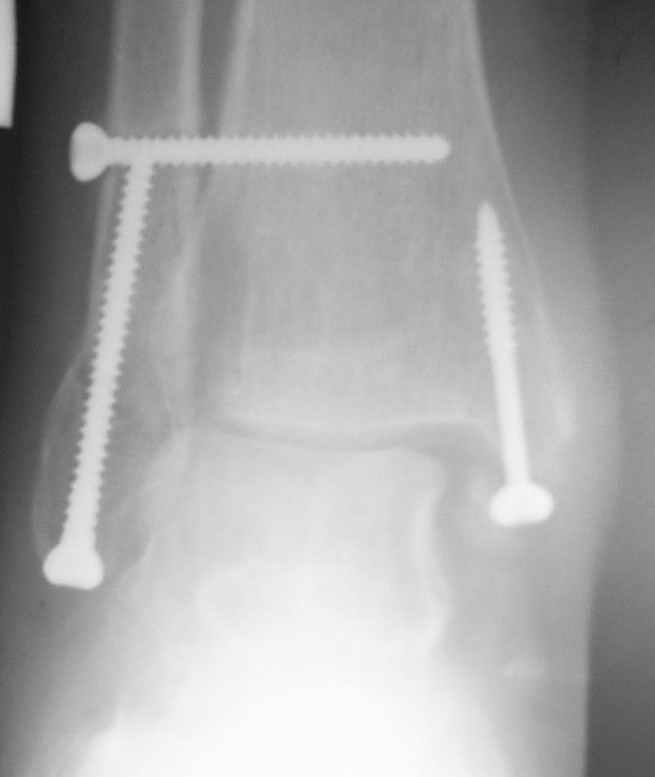

Через месяц

Боковой через месяц